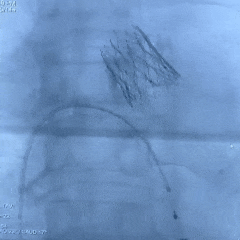

手术过程

根部造影:可见瓣叶钙化,几乎无反流

20mm球囊扩张,无腰,球囊轻微滑动

瓣膜系统定位

瓣膜展开后造影评估,深度可,无明显瓣周漏

多角度造影评估:瓣膜深度形态合适,冠脉灌注良好

脱钩后造影:瓣膜无位移,同轴性良好,无瓣周漏

术后超声测量

即刻瓣口流速2.2m/s;平均压差9mmHg,手术结束